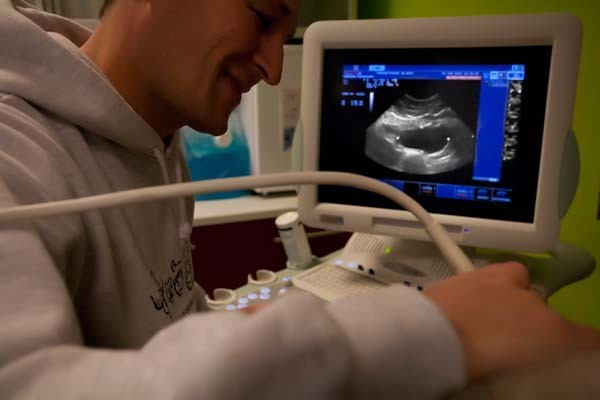

Ultraschall

Bei der Darstellung der inneren Struktur der Weichteile spielt die bildgebende Ultraschall Diagnostik ihre Trümpfe aus. Mit einer variablen Frequenz von 5,5 bis 8 MHz und Schallköpfen in verschiedenen Größen und Formen kann bei unserem Gerät der Untersuchungsbereich an unterschiedliche Gewebetypen und Körpermaße angepasst werden. Dadurch ist eine schmerzfreie und gesundheitlich unbedenkliche Untersuchung verschiedenster Tierarten - vom Axolotl bis zum Schäferhund - möglich.